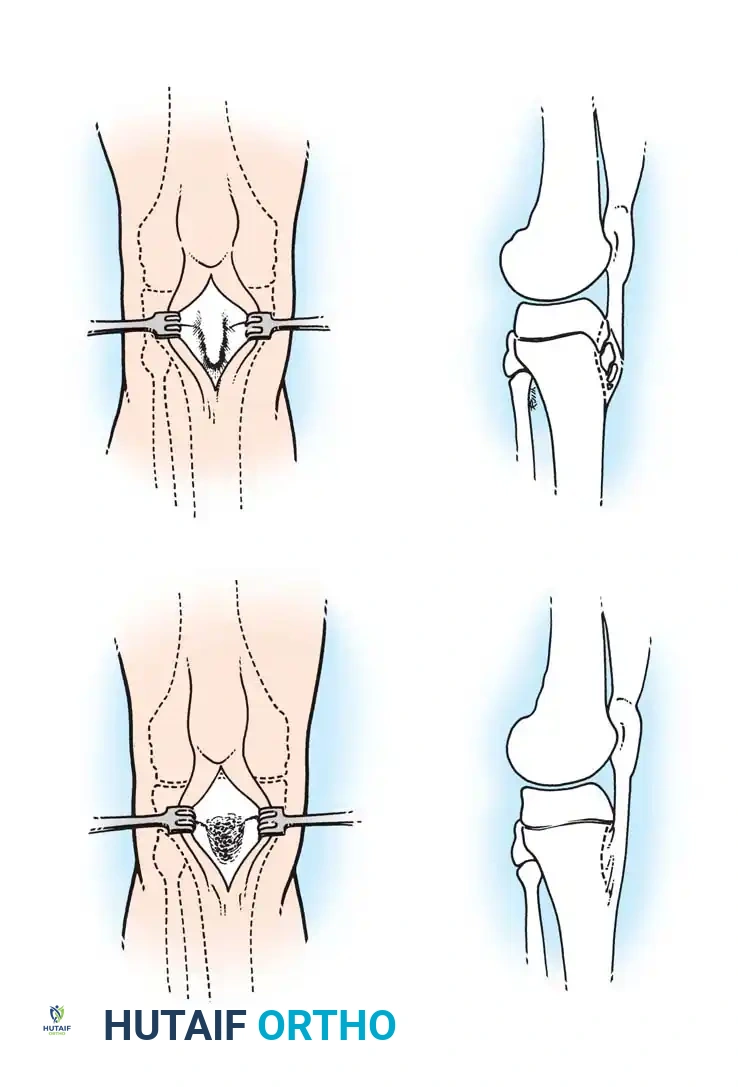

Step-by-Step: Dorsal Wedge Osteotomy

The goal of the dorsal wedge osteotomy is to rotate the healthy plantar articular cartilage dorsally to articulate with the proximal phalanx, effectively removing the necrotic dorsal lesion from the primary weight-bearing axis.

- Positioning and Approach: The patient is positioned supine. A dorsal longitudinal incision is made centered over the affected metatarsophalangeal (MTP) joint. The extensor tendons are retracted laterally.

- Joint Preparation: A dorsal capsulotomy is performed. The joint is inspected, and any loose bodies or hypertrophic synovium are excised.

- Osteotomy Execution: Using a microsaw, a dorsal-based wedge of bone is resected from the metatarsal neck, just proximal to the articular surface. The wedge must include the necrotic dorsal cartilage.

- Closure and Fixation: The osteotomy is closed by dorsiflexing the distal fragment, bringing the healthy plantar cartilage into the functional joint space. The osteotomy is rigidly fixed using a threaded K-wire or a low-profile micro-screw.

- Postoperative Protocol: The patient is placed in a rigid postoperative shoe, strictly non-weight-bearing on the forefoot for 4 to 6 weeks until radiographic union is confirmed.

Osteotomy for Freiberg infraction: Outline of the bony wedge, resection, closure, and wire fixation.